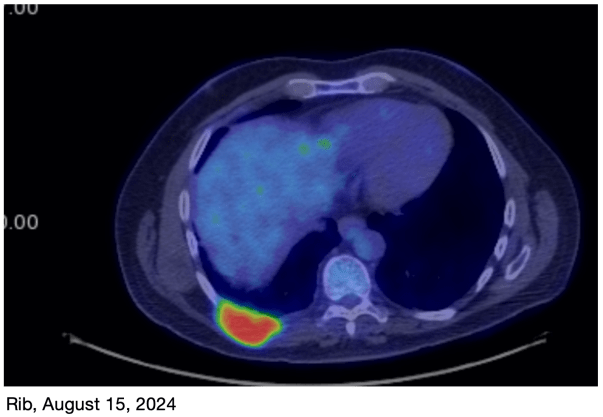

I have some sobering news. I had a PET scan on Tuesday and it appears that the rib tumor is trying to make a comeback. My original treatment plan had just 4 rounds of chemo, and then immunotherapy after that. While the chemotherapy worked well, it appears that the immunotherapy has not been as effective as was hoped.

As you can see in the images, the rib tumor was basically absent in the March 30th image, but has reappeared in the image from this week (July 1st).